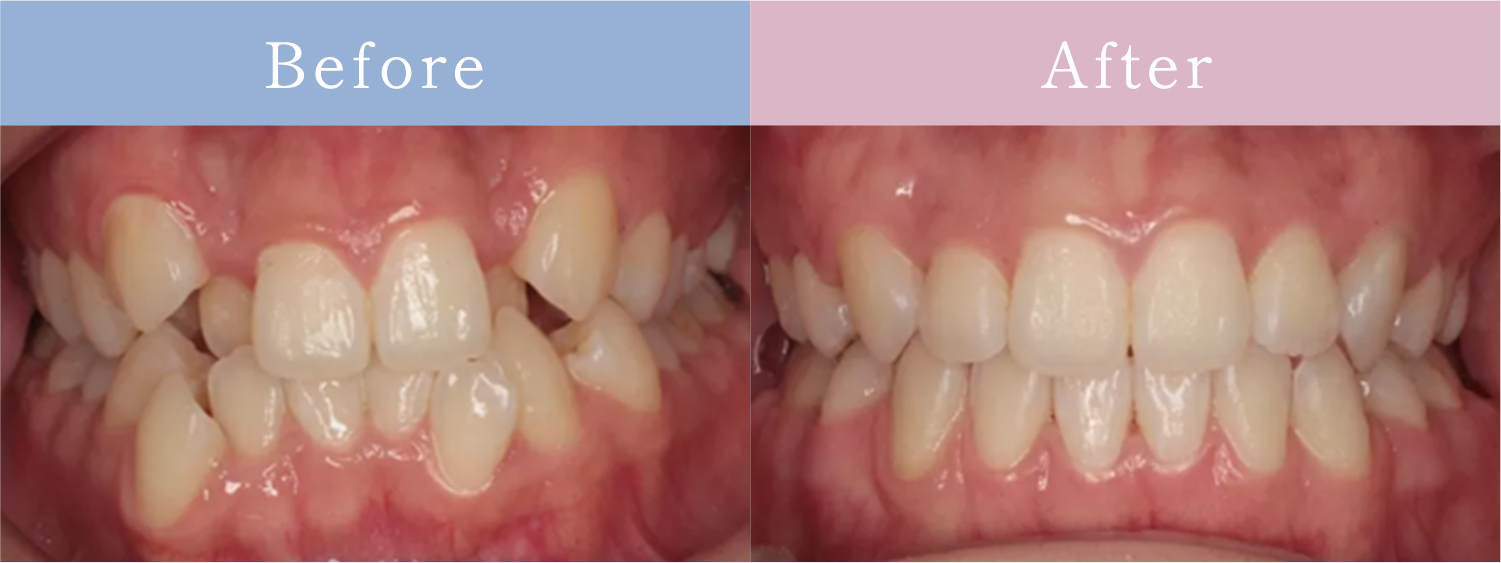

CASE症例

歯並びだけじゃない「お顔全体のバランスまで追求」

歯並びが原因でお顔立ちに

影響を与えている場合は

矯正治療で改善できます